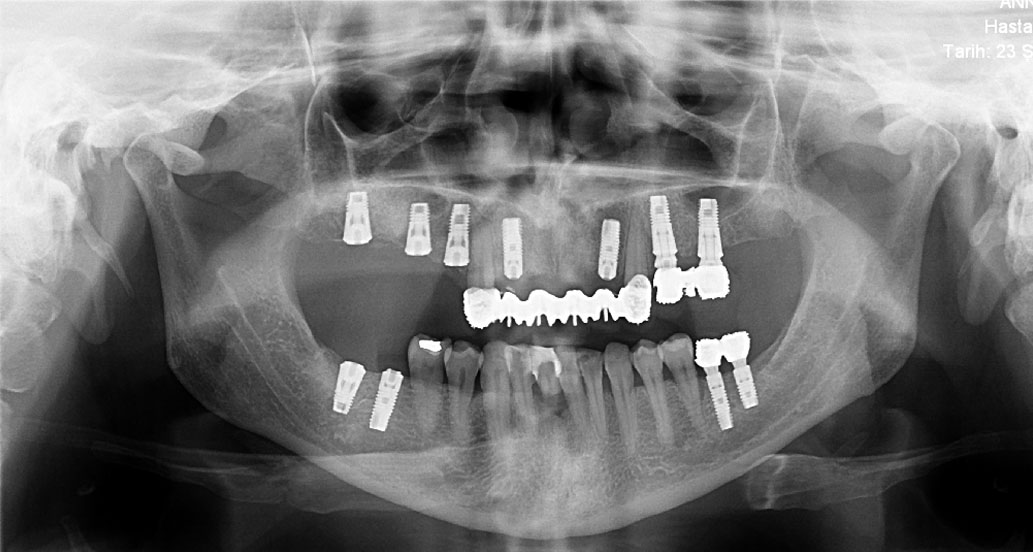

Ýmplant

Protezler

Oral Diagnoz ve Radyoloji